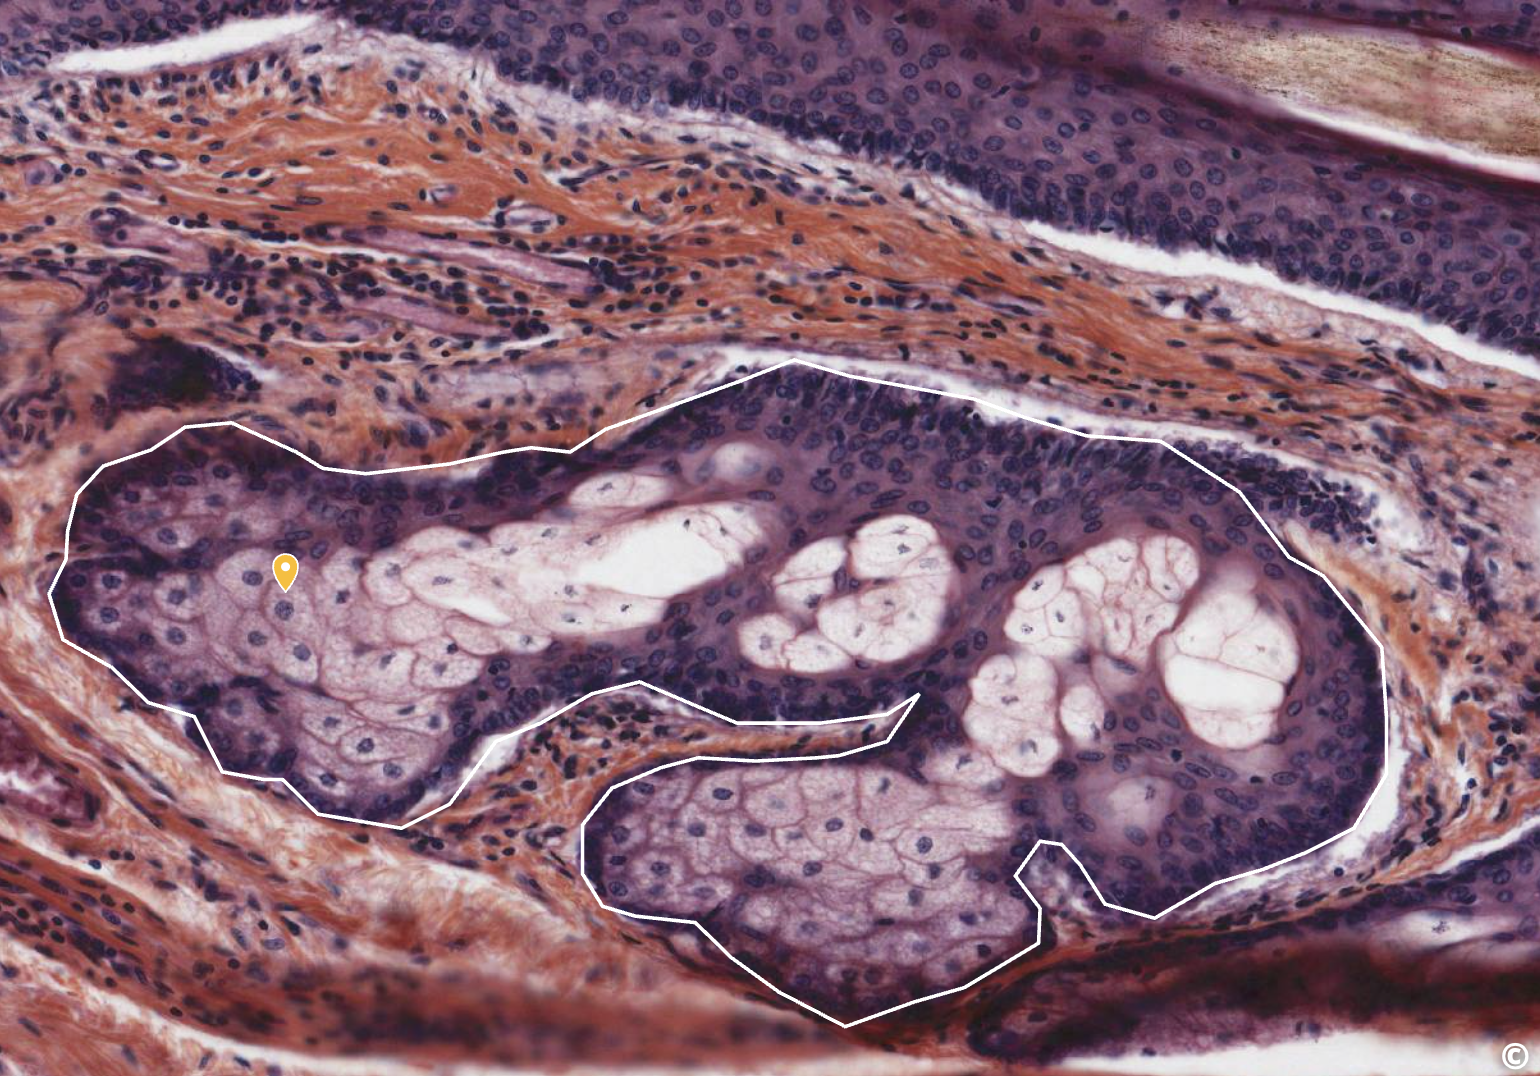

<p>what this</p>

what this

sebaceous gland (branched alveolar/acinar gland)